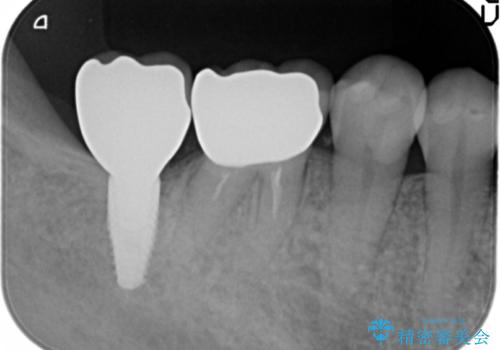

奥歯 インプラントによる機能回復

- 45万円(ストローマンインプラント・骨造成・チタンカスタムアバットメント・ジルコニアクラウン)費用は治療当時の料金となります

最後方臼歯はインプラントを用いることでしっかりと咬合機能を回復することができます。